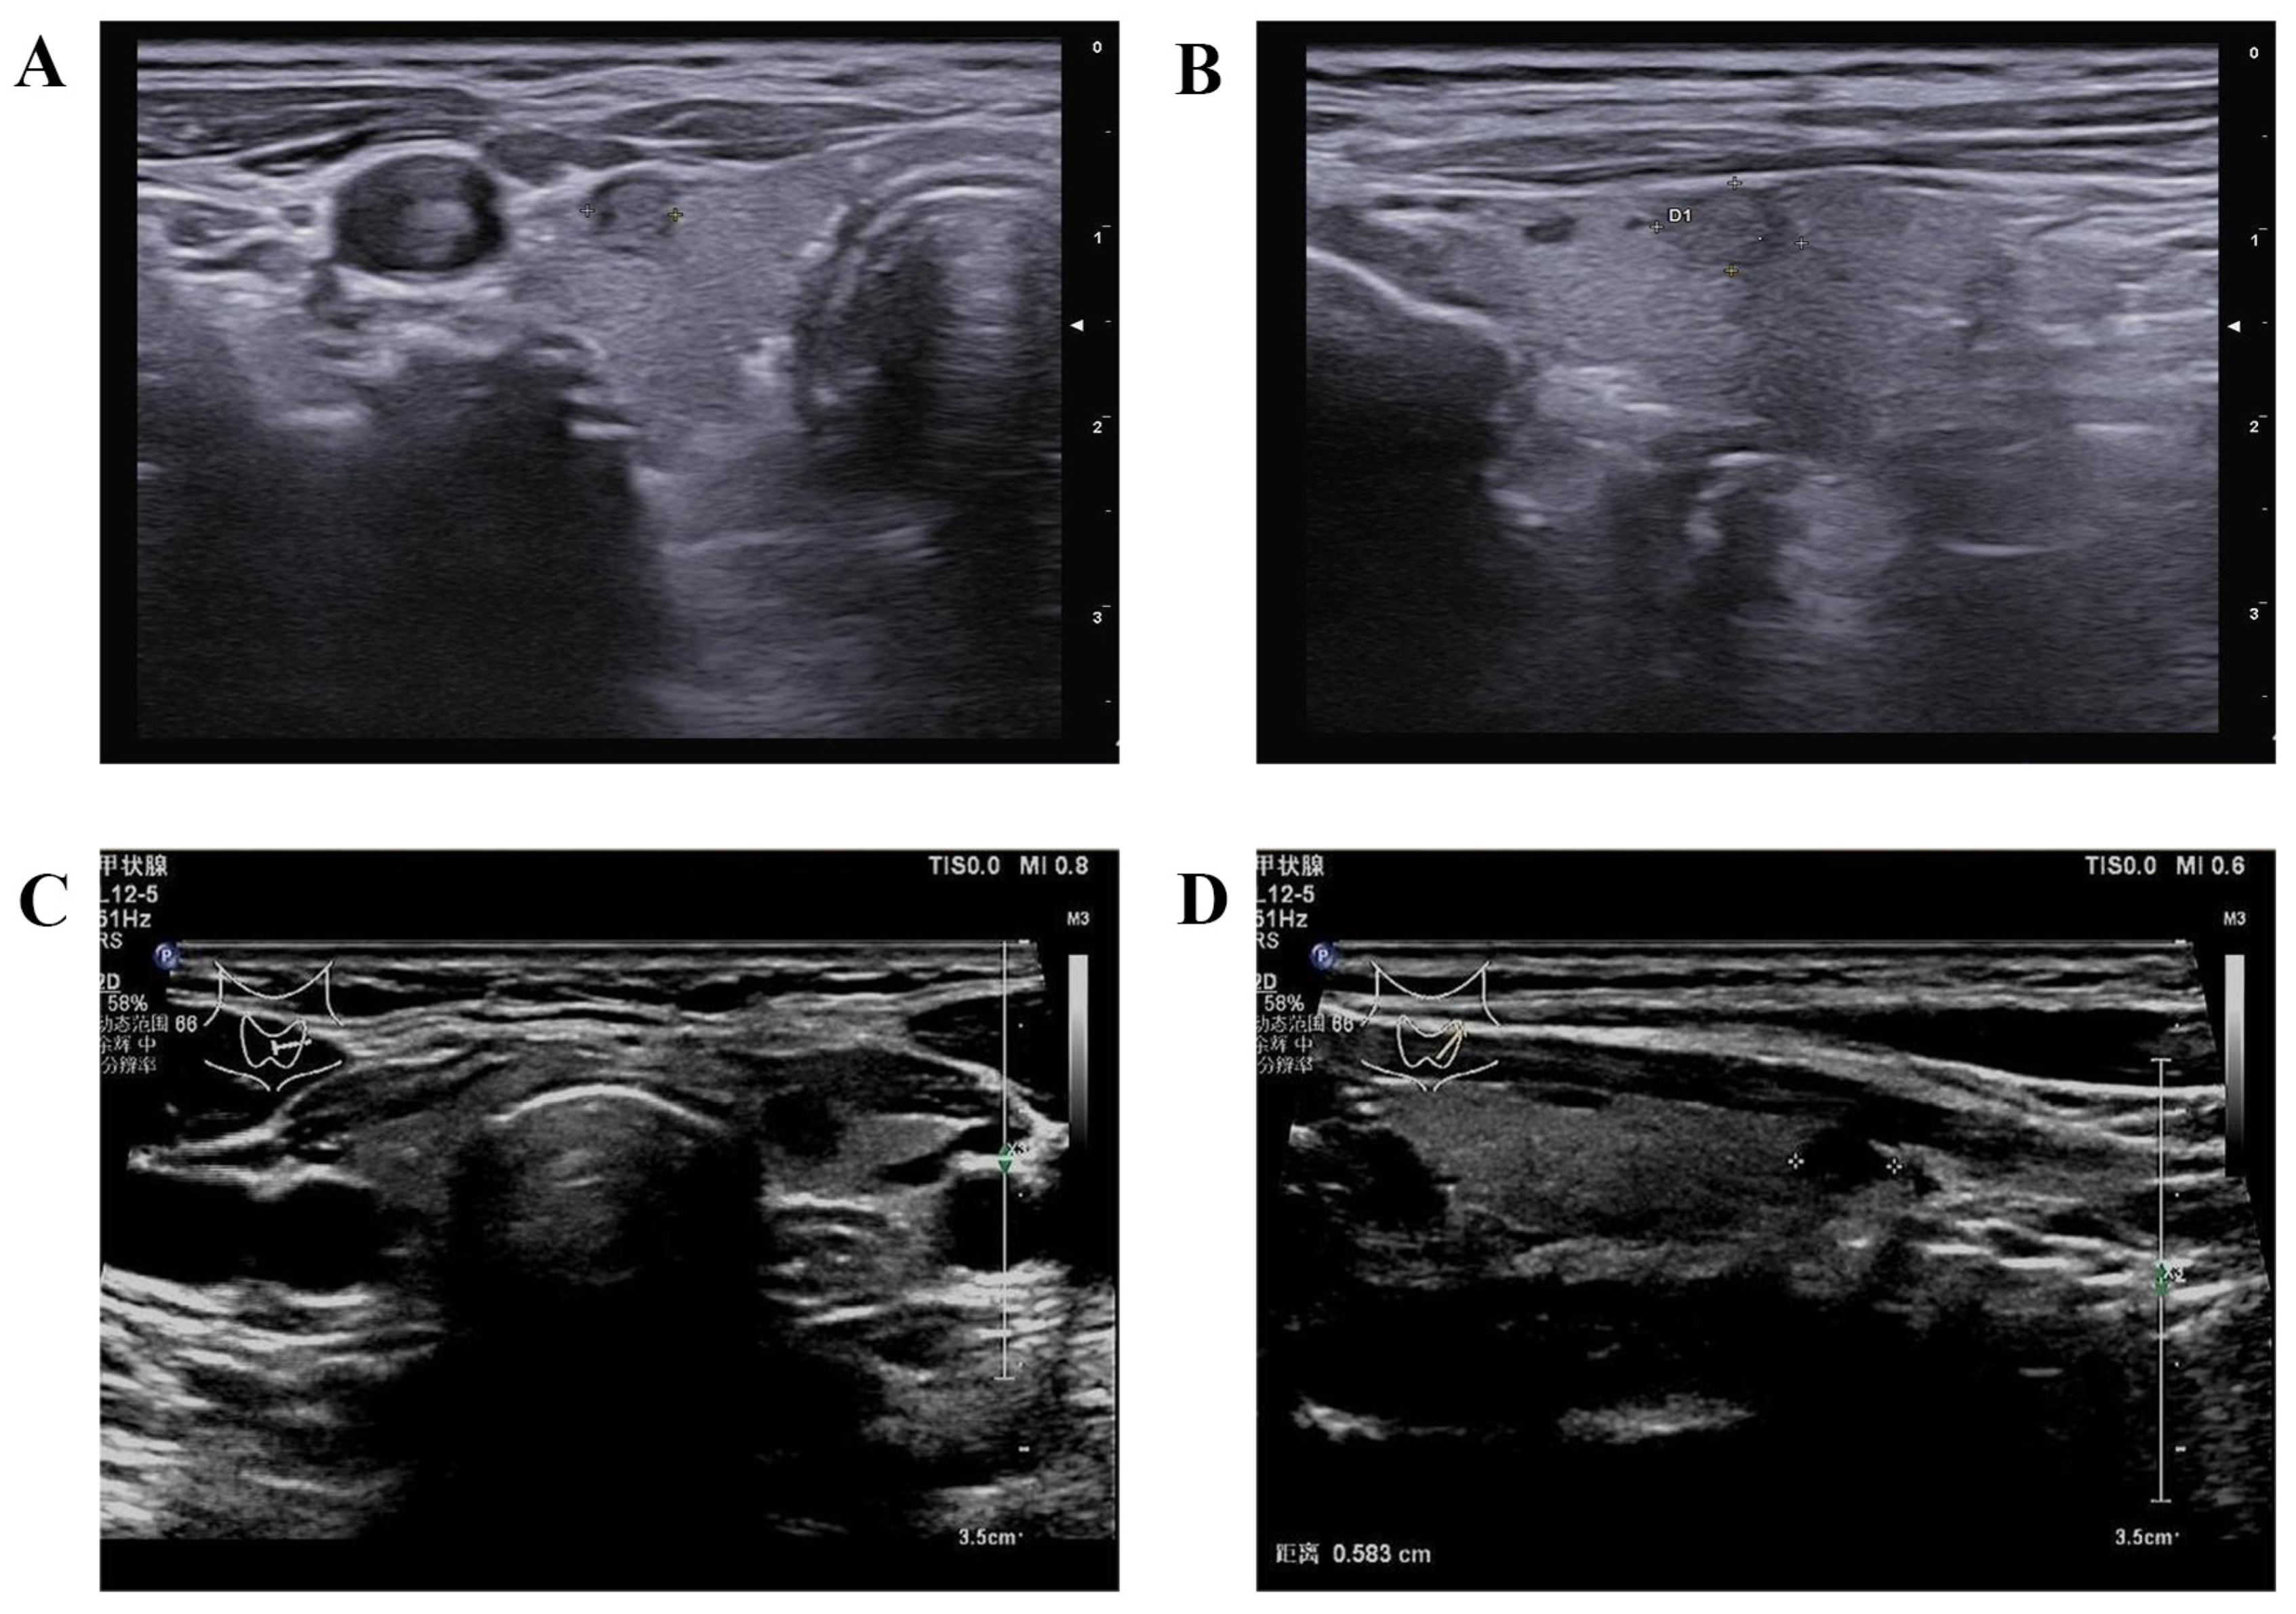

3. Conventional Gray-Scale and Doppler US

4.1. CEUS

4.2. SWE